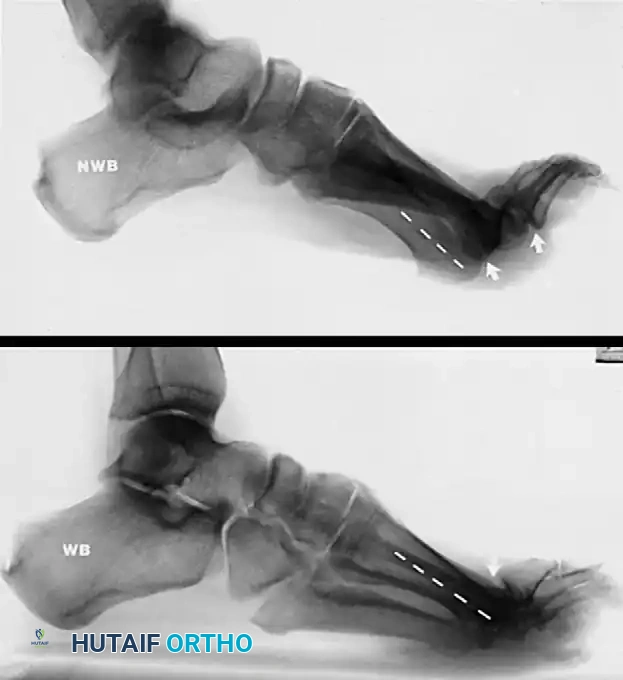

FIGURE 86-20: A, Non–weight bearing view of cavus and claw toe deformities in a patient with Charcot-Marie-Tooth disease. B, On the weight-bearing view, plantar flexion of the first ray is less noticeable, but the clawed hallux remains, indicating a fixed extension contracture at the first metatarsophalangeal joint.

Clinical Pearl: Always compare non-weight-bearing and weight-bearing lateral radiographs. A deformity that partially corrects upon weight bearing suggests a degree of flexibility, whereas a deformity that remains unchanged dictates the need for aggressive bony resection or arthrodesis.